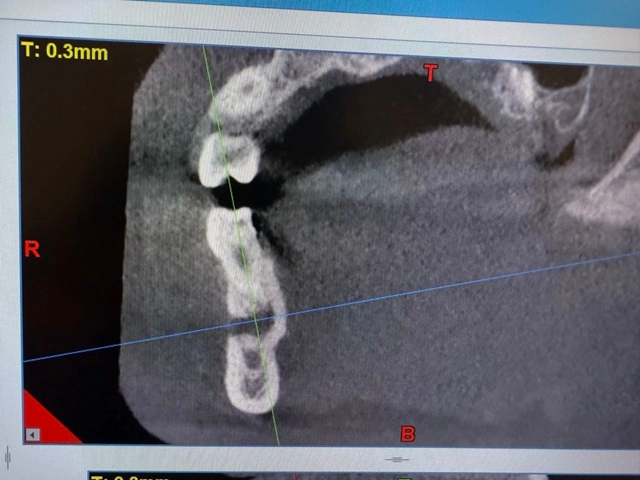

影像学检查进一步揭开真相:根尖X线片发现45牙根尖有5mm×7mm的暗影;CBCT清晰显示颊侧骨板已被破坏,感染顺着咬肌前间隙扩散,形成了的脓腔,最终突破皮肤形成面部瘘口。血常规检查中白细胞、中性粒细胞和CRP等感染指标均显著升高,证实了严重的细菌感染状态。

术前影像学资料